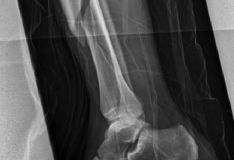

Nail Insertion and Distal Interlocking

Following meticulous preparation, the canal is reamed sequentially. Care must be taken not to over-ream the distal segment, which could compromise the already tenuous metaphyseal bone stock. The nail is inserted gently; forceful impaction is strictly avoided to prevent displacing the previously secured articular block.

Distal interlocking must be maximized. The surgeon should utilize a minimum of three, and ideally four, distal locking screws, engaging the bone in multiple planes (e.g., two medial-to-lateral, one anterior-to-posterior). This multi-planar fixation is essential to control rotation and angular displacement in the wide metaphyseal bone.